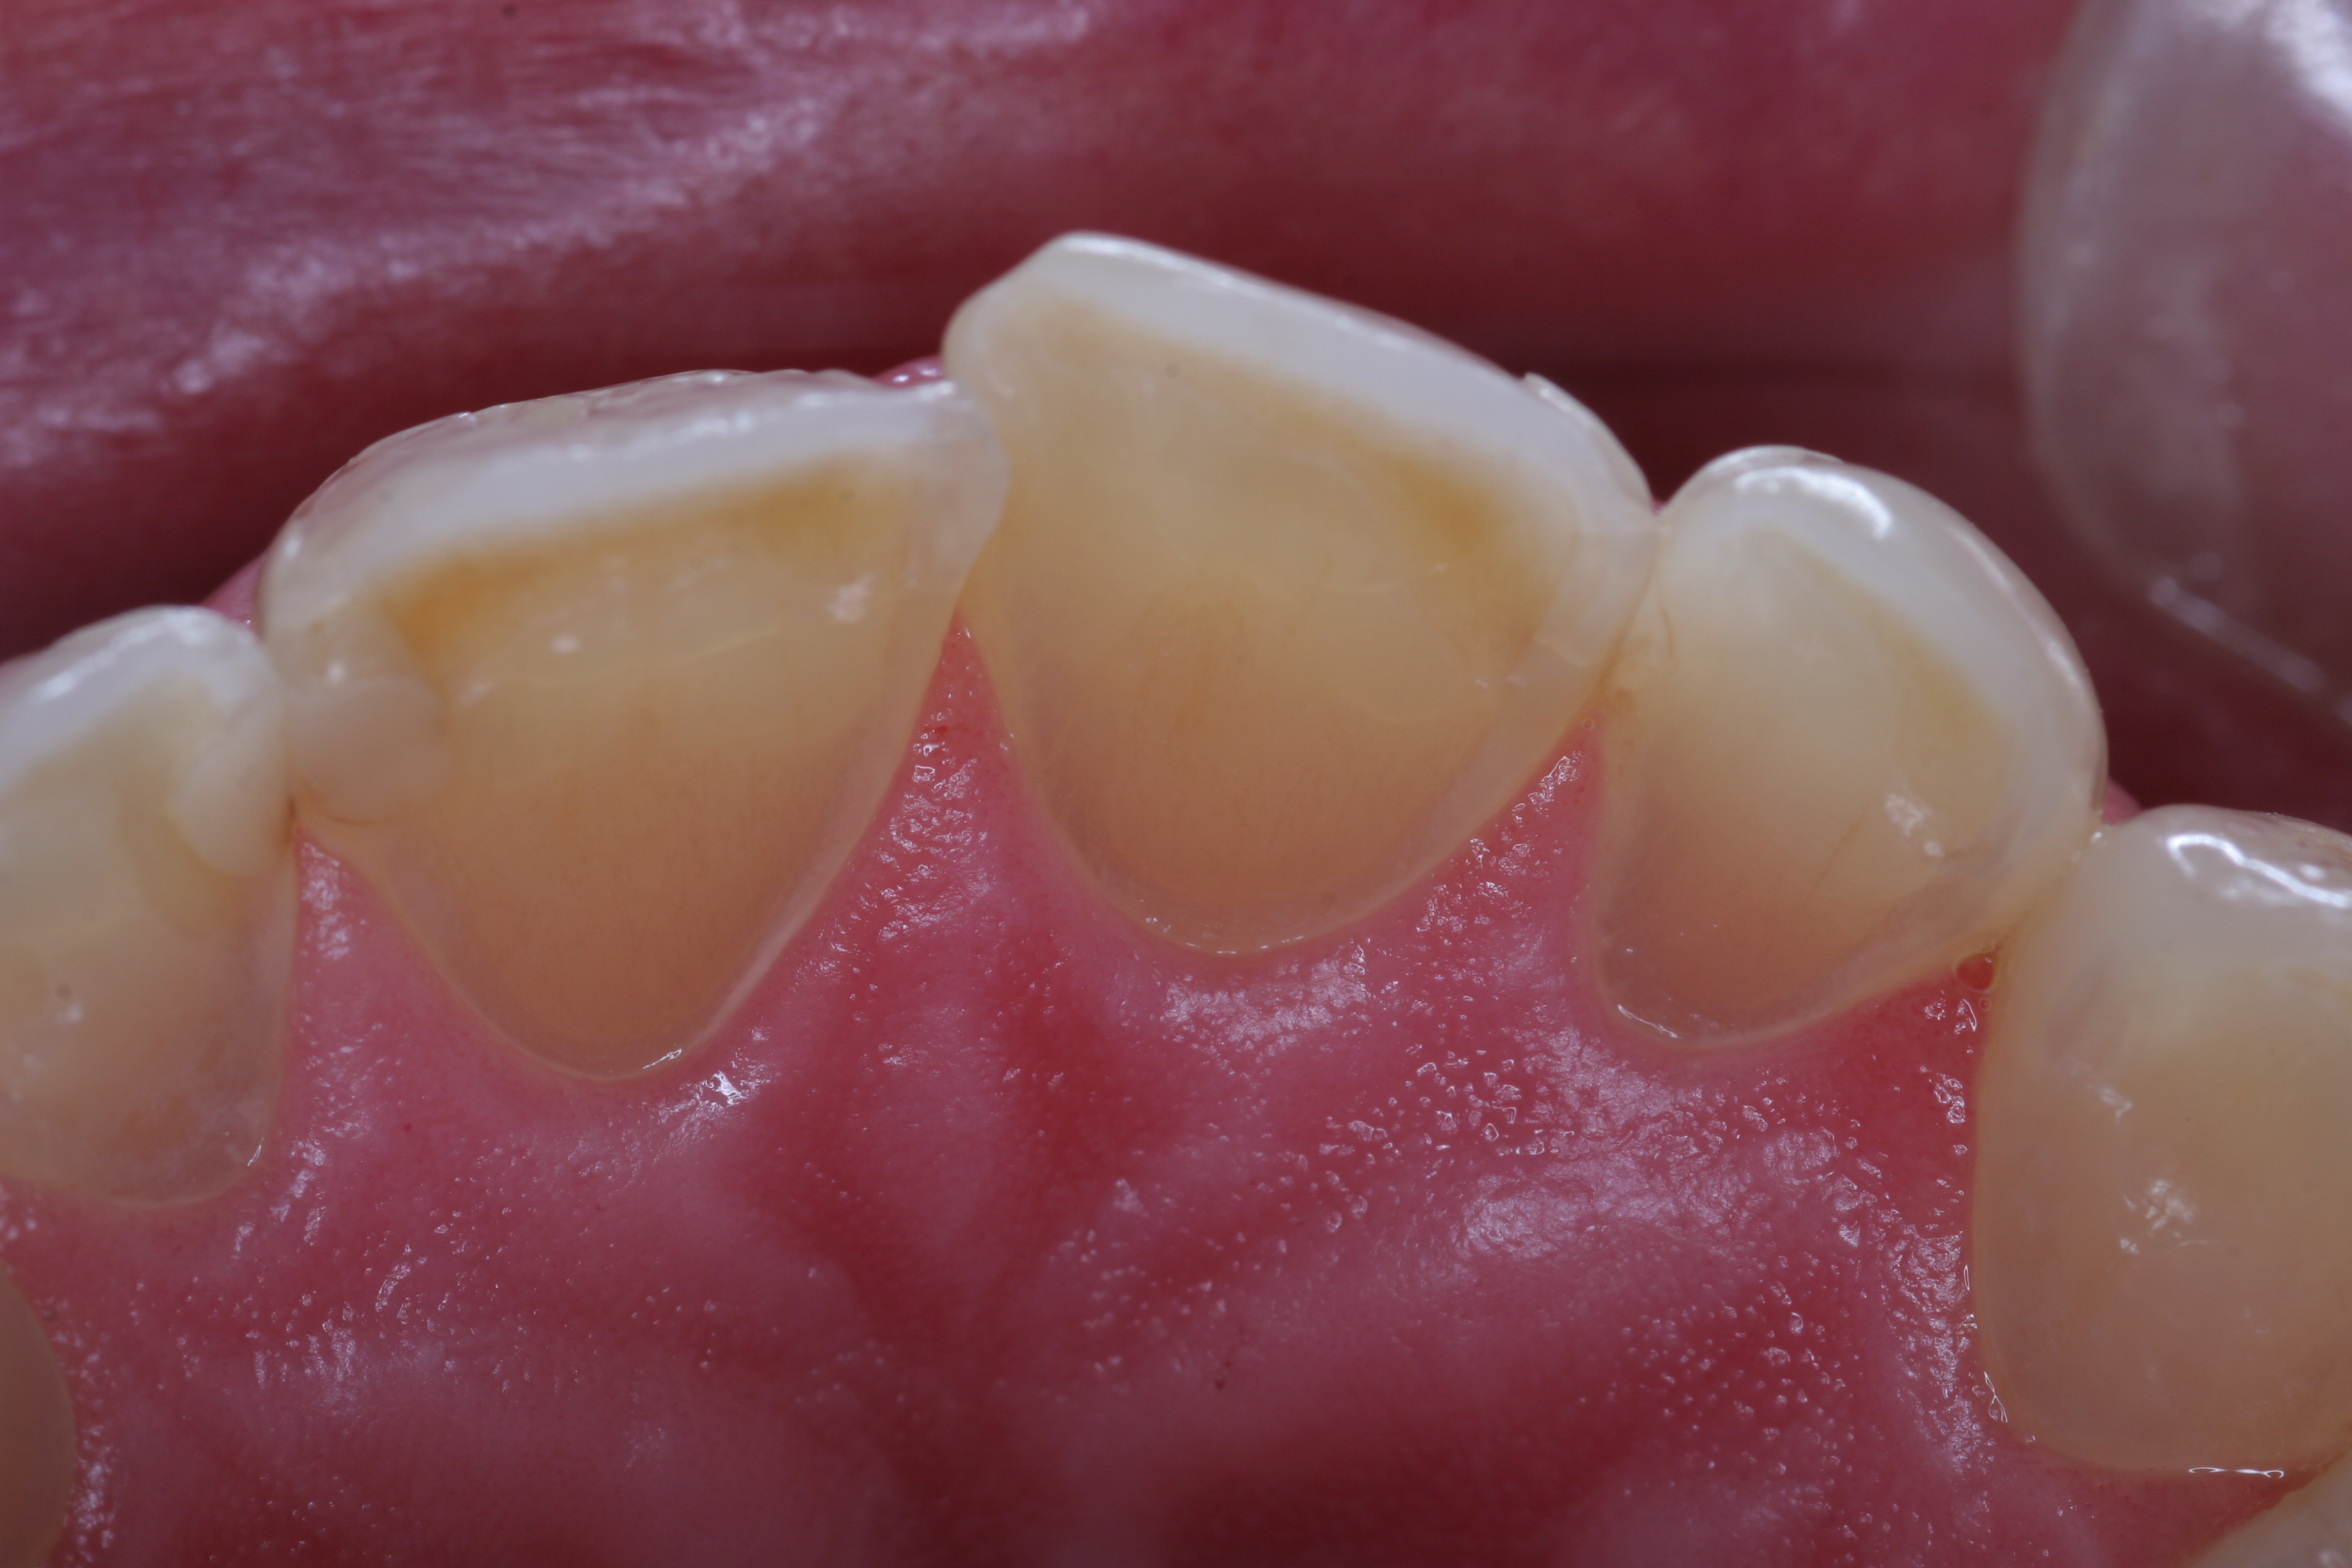

(5.) The anterior teeth must have sufficient lingual contour to allow immediate disclusion of the posterior teeth.

Figure 5